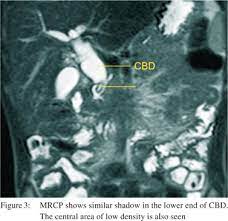

Multiple worms in CBD are well known, and ultrasound is considered a very useful modality for diagnosis and for follow-up. Also, there can be worms in bile ductules that may lead to the persistence of symptoms despite of CBD clearance. Follow-up ultrasound is thus mandatory if symptoms persist.